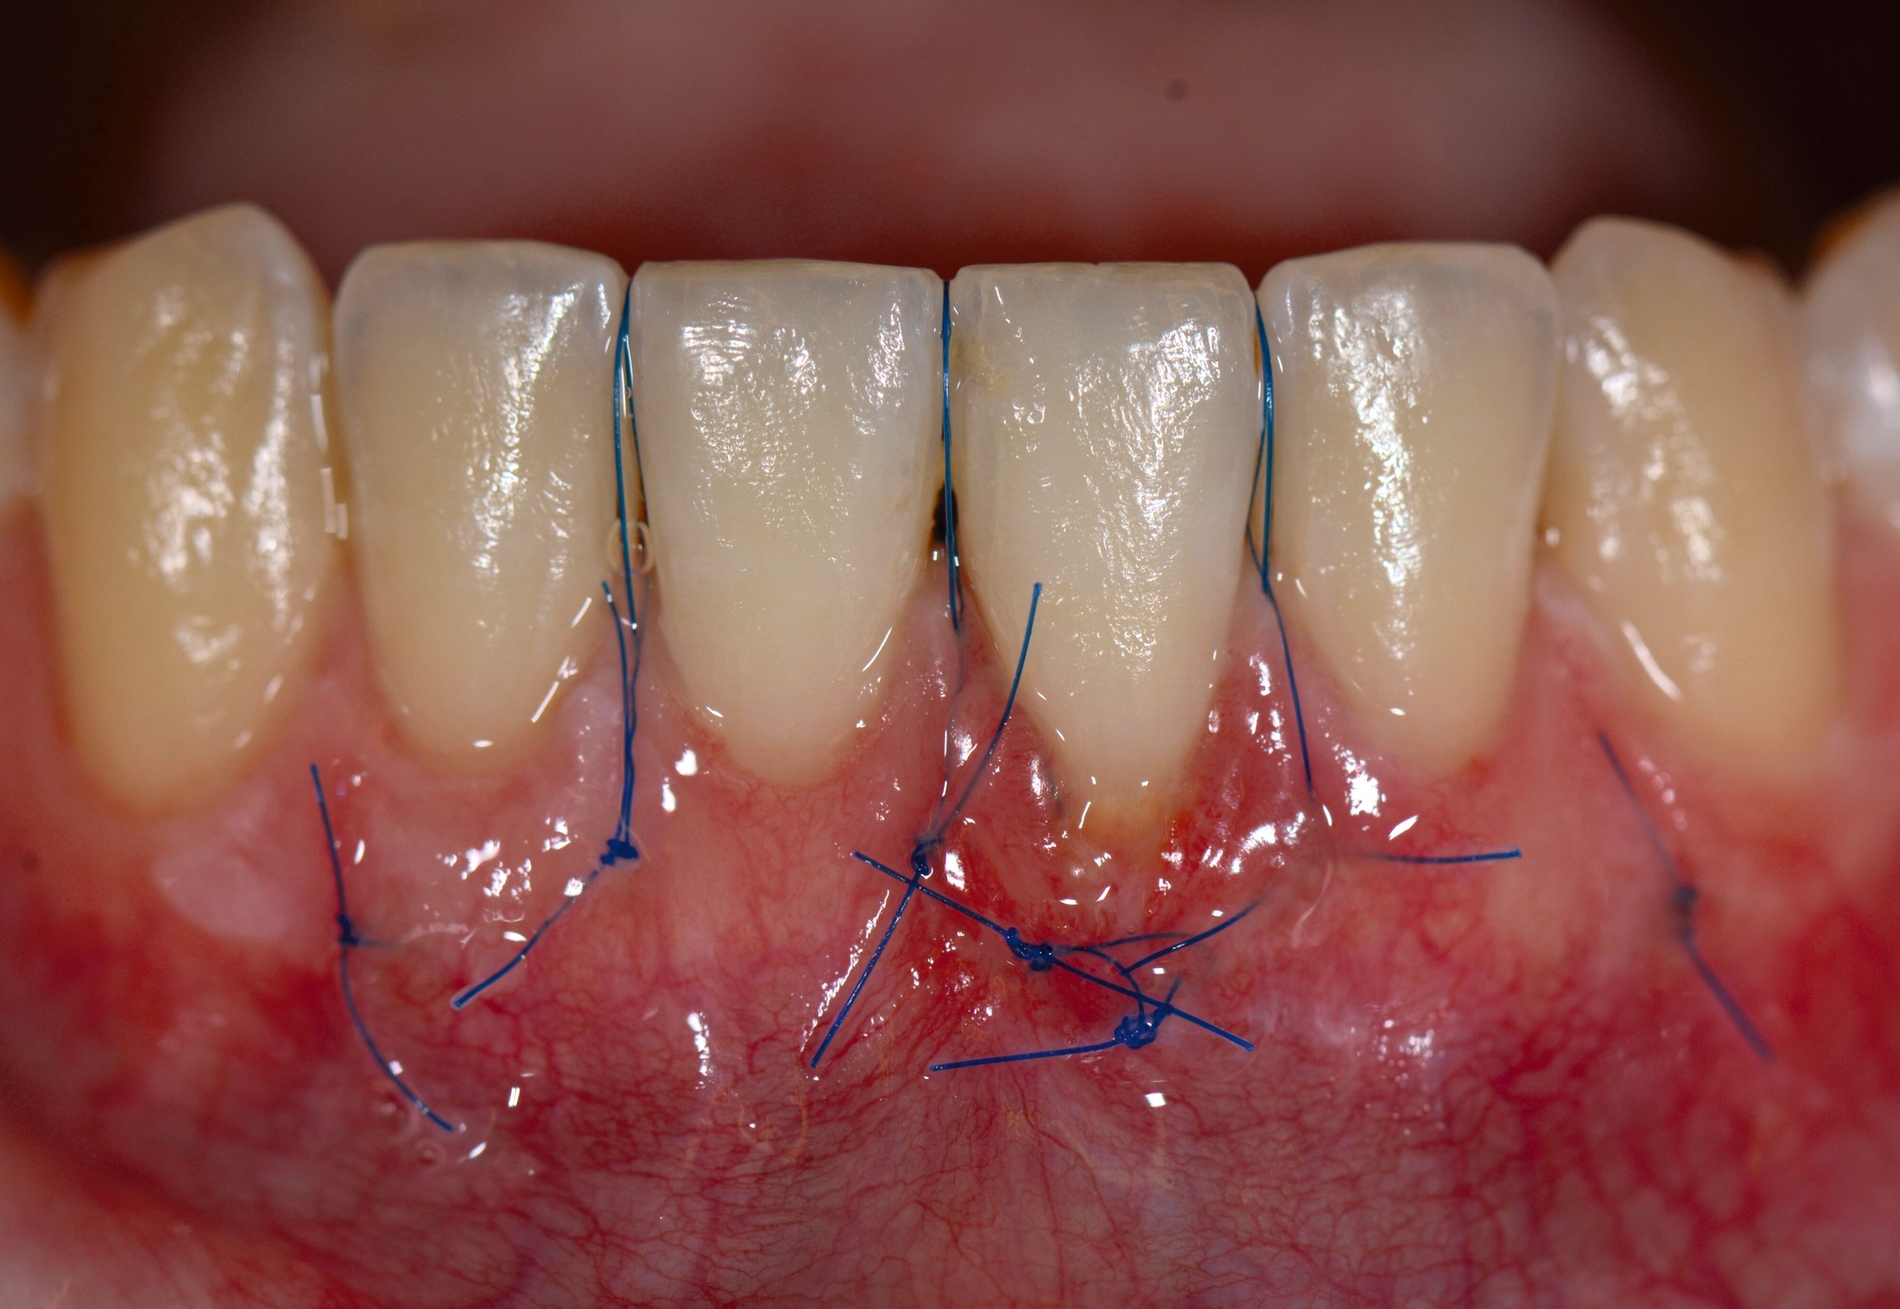

Das „klassische“ BGT wurde bereits in den 1970er-Jahren beschrieben und ist besonders verbreitet bei der Behandlung von gingivalen Rezessionen und der Weichgewebsaugmentation um Implantate. Das Transplantat wird durch eine sorgfältige Präparation unterhalb des Epithels vom lateralen und eher anterioren Gaumen gewonnen. Durch den Erhalt des bedeckenden Gewebes soll eine primäre Heilung sichergestellt werden. Die Höhe des Gaumendachs und somit die Entfernung zur Arteria palatina sowie die Dicke der Schleimhaut, vor allem über den palatinalen Wurzeln der Molaren zusammen mit den Rugae des anterioren Gaumens, sind die limitierenden Faktoren bei dieser Technik.

Trotz des Verbleibs des Epithels kann es zu sekundärer Wundheilung mit entsprechender Morbidität postoperativ kommen, besonders bei Techniken, die mehrere Inzisionen beinhalten, wie den sogenannten Trap-Door-Techniken, so dass sich die „Single-Incision-Technik“ durchgesetzt hat [Fickl et al., 2014]. Gegen eine übermäßige Blutung und postoperative Morbidität empfiehlt sich klinisch die routinemäßige Anwendung einer Verbandplatte, entweder in der Tiefziehtechnik oder präoperativ mittels eines Thermoplasts, so dass sich früh ein stabiles Blutkoagel bildet und die Wundheilung an der Entnahmestelle ungestört ablaufen kann. Dadurch wird die Morbidität klinisch deutlich reduziert. Das sBGT zeigt ästhetisch sehr gute Ergebnisse mit Blick auf Oberflächenstruktur sowie Farbe und kann unter anderem im Rahmen der Envelope- oder Tunneltechnik oder auch über einer Extraktionsalveole bewusst exponiert belassen werden, um zusätzlich befestigte Gingiva zu gewinnen.